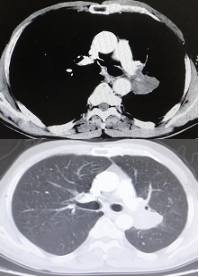

影像学-增强CT检查:右肺上叶中心型肺癌伴阻塞性肺炎,左肺下叶占位性病变,长径:2.9cm;纵隔及双肺门淋巴结转移,较大位于7组,短径1.1cm,肝脏多发点状异常密度影,考虑转移,多发骨转移。

CT检查——基线

影像学-增强CT检查:治疗4周期后,病灶缩小31%,疗效评估为PR。

靶病灶:左肺病灶明显缩小;

非靶病灶:右肺门病变缩小。

CT检查——治疗4周期后